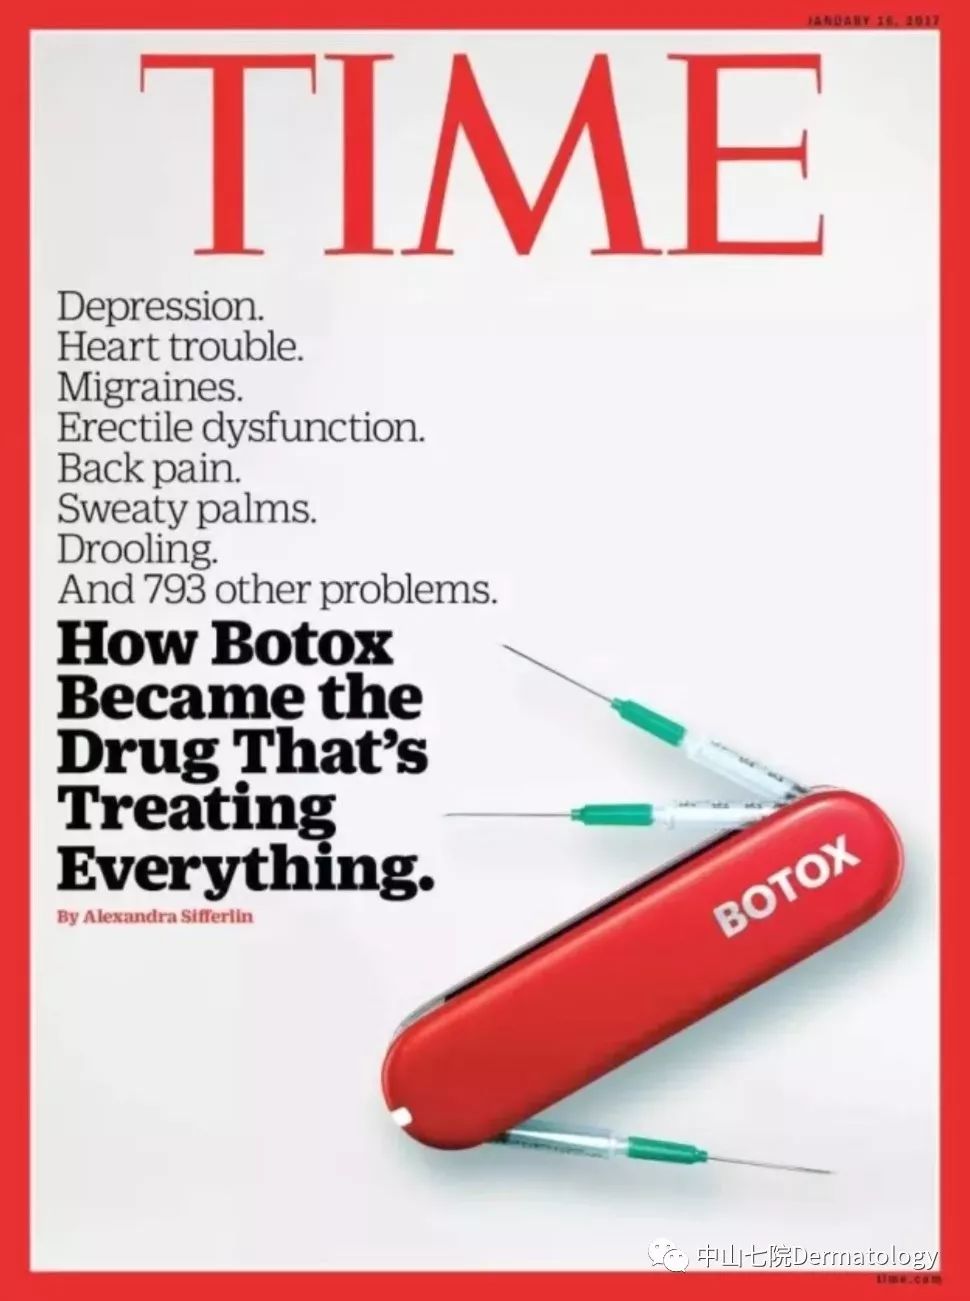

肉毒素因其出众的疗效甚至登上了2017年美国时代周刊的封面故事。